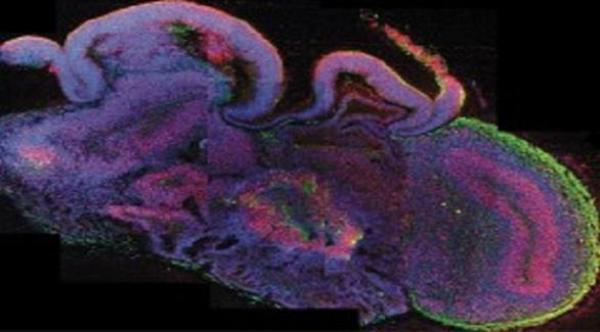

تصوير جديد للدماغ

وتمثل الاكتشاف الثاني بتقنية جديدة لتصوير الدماغ، تعمل على جعل أنسجة الدماغ مرئية، مما يزيل أكبر عقبة أمام الطريقة التقليدية لتصوير الدماغ، إذ تتسبب جزيئات الدهون التي تشكل الأغشية الخلوية ببعثرة الضوء، مما يجعل أنسجة المخ مبهمة، بينما تعمل التقنية الجديدة على استبدال الدهون بجزئيات مكونة من مادة هلامية واضحة، وهو ما يجعل أنسجة الدماغ شفافة ومرئية.

وتمحور الاكتشاف الرابع حول تسخير العلماء خلايا تدعى الخلايا الجذعية المحفزة لتؤدي دور كل الأعضاء الحية بالغة الصغر، وتبين عند تحليل أدمغة الناس البدائيين أن أنسجتها وبنيتها متشابهة بشكل مدهش على الرغم من أنها لا تحوي شرايين للدم، ولا تنمو أكبر من بذور التفاح، واستخدمها الباحثون لاكتساب رؤى جديدة عن صغر الرأس، وهو الشرط الذي يمنع نمو الدماغ لحجمه الكامل.